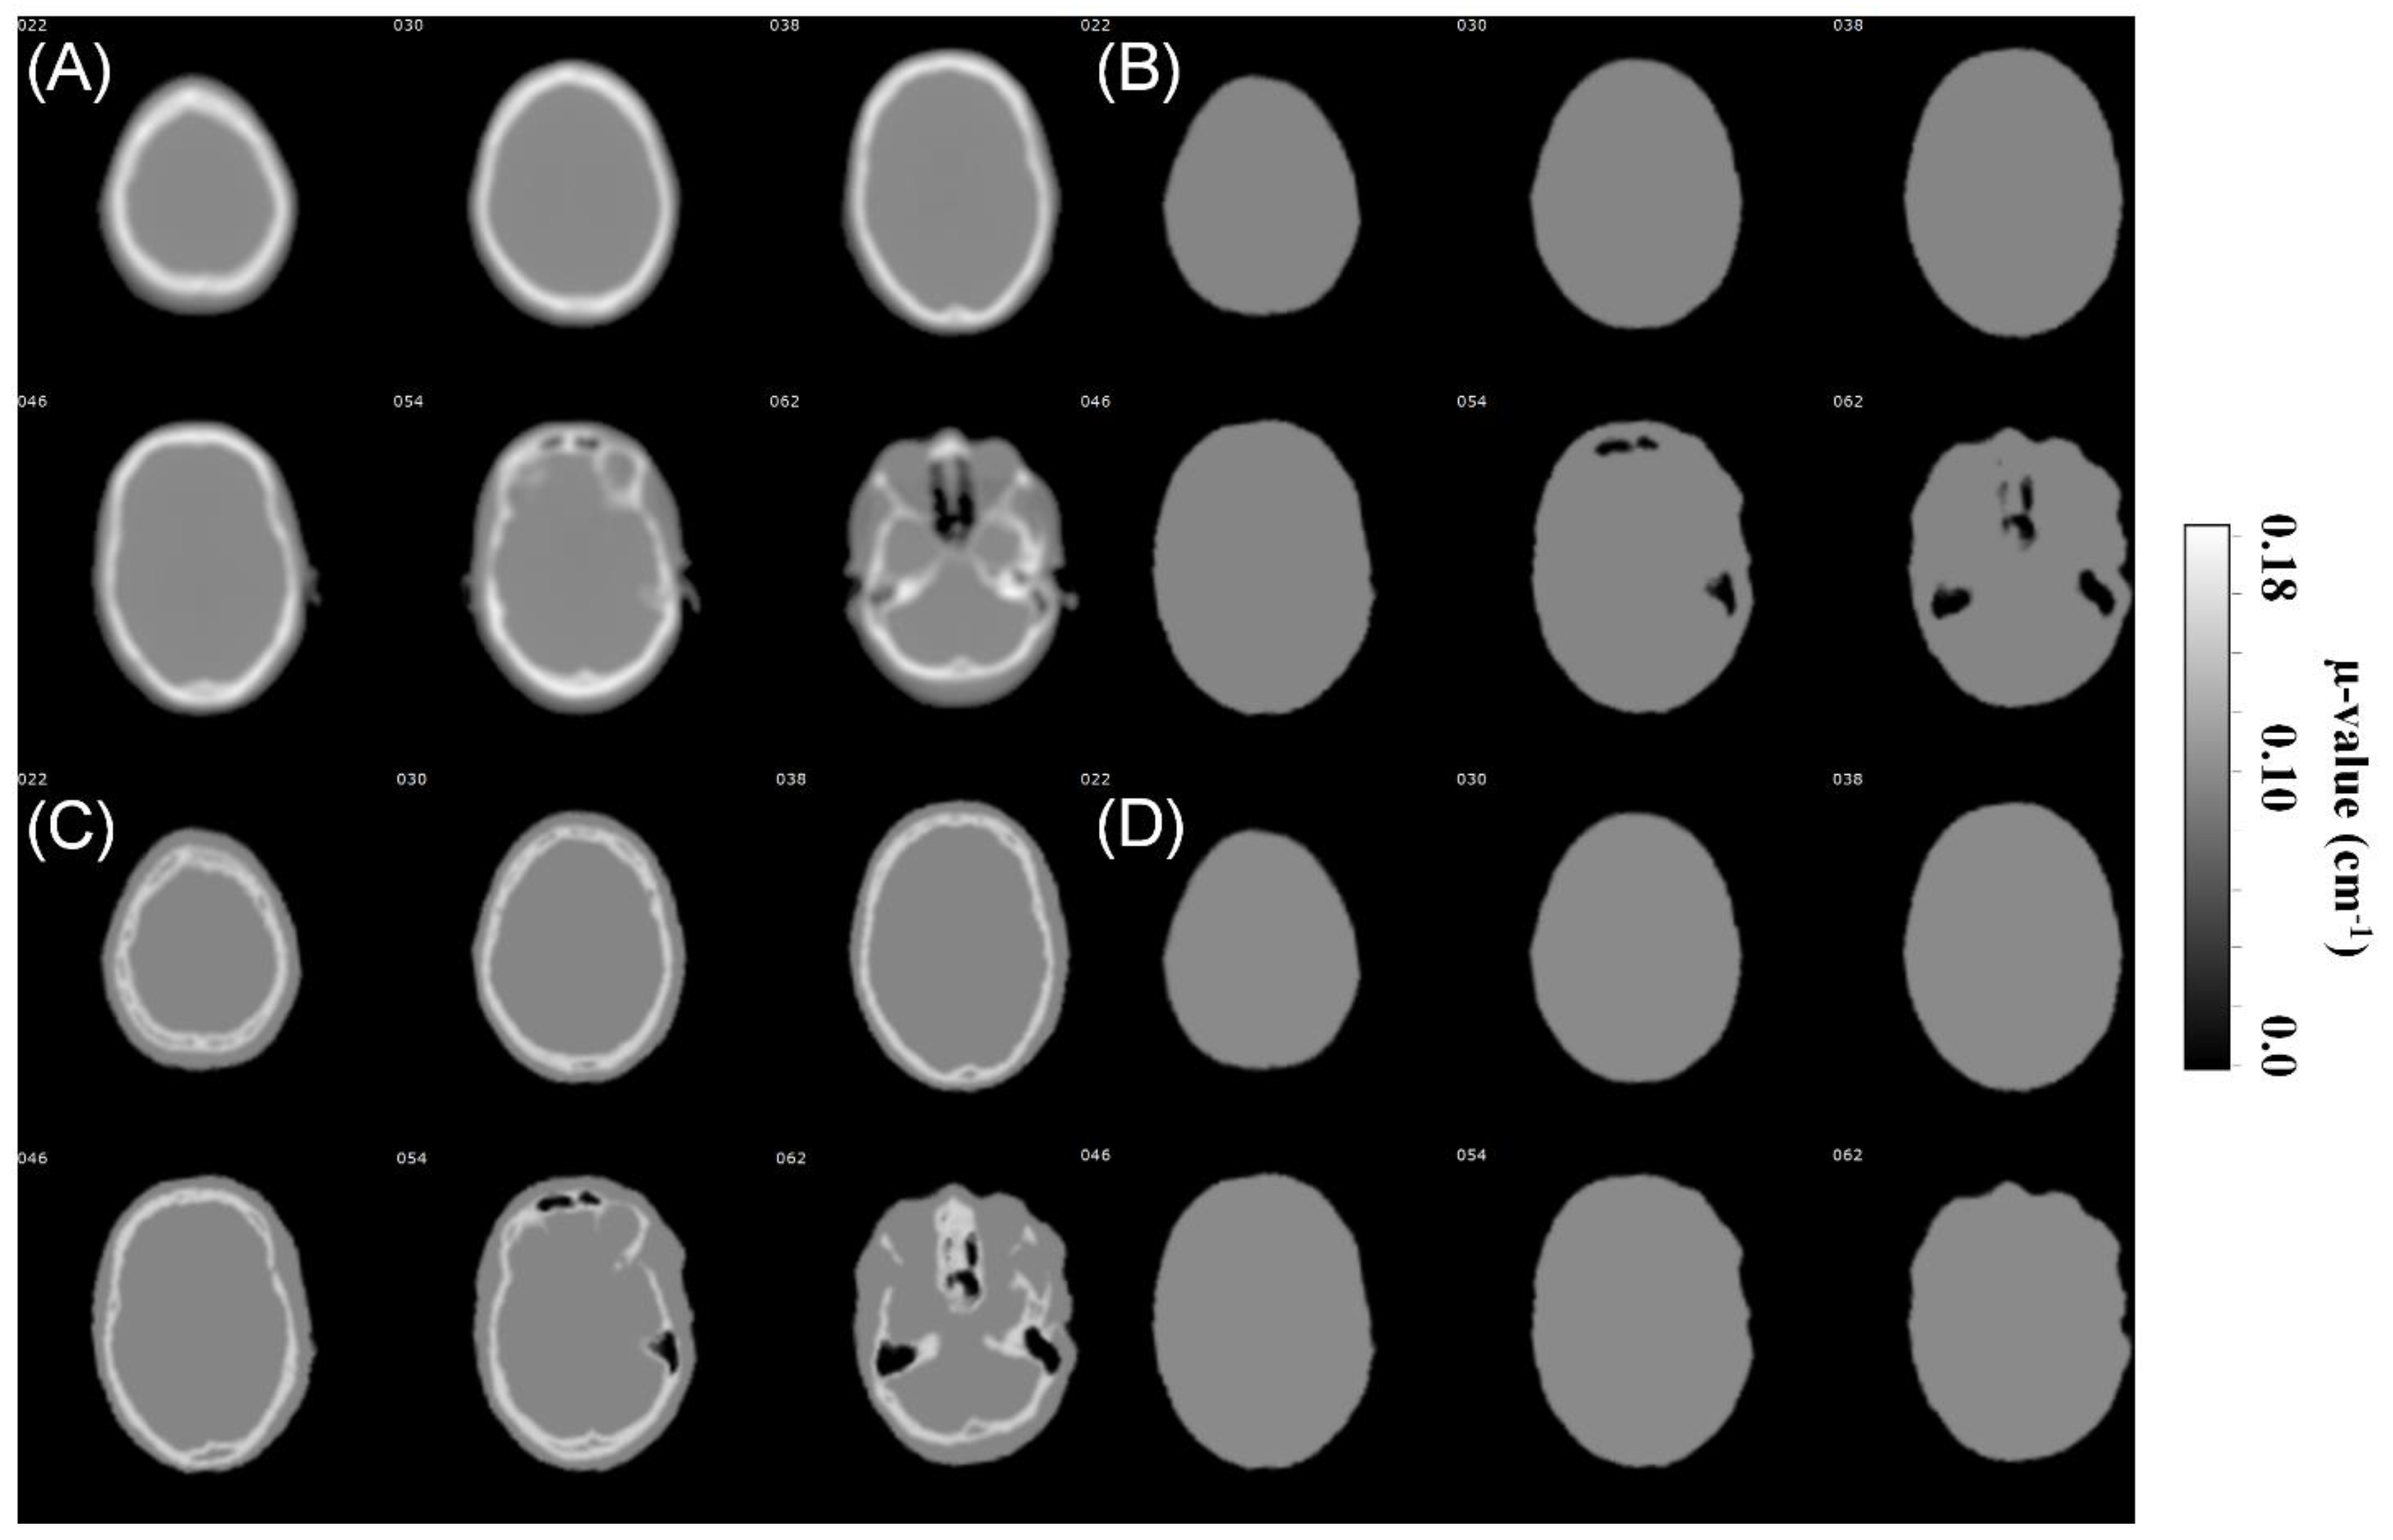

2.2. CTAC Data

2.3. MRAC Data